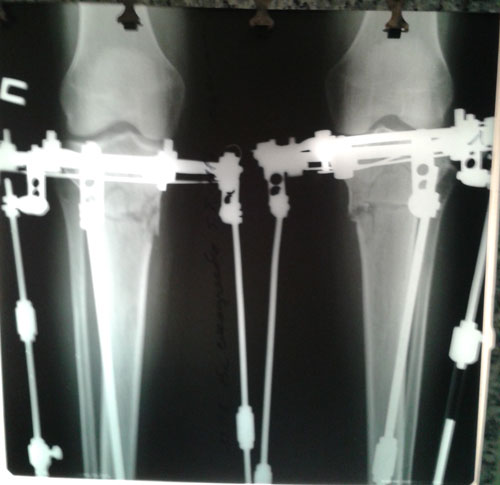

Дата операции 23.01.2015г.

Дата снятия аппаратов 28.04.2015г.

Срок лечения 95 дней.